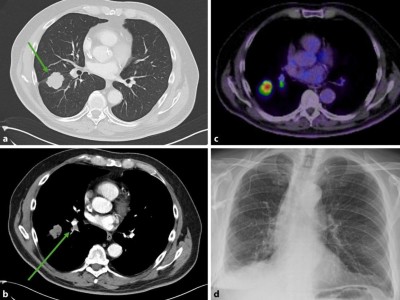

Einsatz von funktioneller Bildgebung zur Therapieplanung

Funktionelle Bildgebung hat in den letzten Jahren immer mehr Bedeutung in der onkologischen Therapieplanung gewonnen. Die Positronenemissionstomographie (PET), meist kombiniert mit einer Computertomographie (PET-CT), ermöglicht häufig nicht nur …

Operation/© andrys lukowski / stock.adobe.com (Symbolbild mit Fotomodell), Arzt impft Patient/© FG Trade / Getty Images / iStock (Symbolbild mit Fotomodell), Koloskopie/© Kzenon / stock.adobe.com (Symbolbild mit Fotomodellen), Bestrahlungsplans einer Wirbelsäulenmetastase eines oligometastasierten Prostatakarzinoms/© Springer Medizin Verlag GmbH, Blutprobe wird bei Patient abgenommen/© Tashi-Delek / Getty Images / iStock(Symbolbild mit Fotomodellen), Endobronchialer Befund mit exophytischem Tumor im Bereich des rechten Oberlappens/© Möller, M., Schütte, W. / all rights reserved Springer Medizin Verlag GmbH, Eine ältere Frau bekommt eine intravenöse Therapie/© peopleimages.com / stock.adobe.com, Mann gibt Anweisungen auf Baustelle/© Oliver Raupach - Fotolia (Symbolbild mit Fotomodell), CT-Thorax mit Verdacht auf Lungenkrebs/© Springer Medizin Verlag GmbH, Nicht-kleinzelliges Bronchialkarzinom/© windcatcher / Getty Images / iStock, Immuncheckpointinhibitoren binden an Krebszelloberflächenproteine /© Juan Gärtner / stock.adobe.com, Einem Mann wird Fieber gemessen/© eggeeggjiew / Getty Images / iStock (Symbolbild mit Fotomodell), Mann stützt den Kopf in die Hände/© Charday Penn / Getty Images / iStock (Symbolbild mit Fotomodell), Bronchoskopie/© Schroll S et al. / all rights reserved Springer Medizin Verlag GmbH, NSCLC in der PET-CT/© A. Schäffler, Bestrahlung eines Lungenkarzinoms/© Springer Medizin Verlag GmbH, Bildgebung einer rechts pulmonalen Raumforderung der Lunge/© Klotz, L.V., Welcker, K. / all rights reserved Springer Medizin Verlag GmbH, Search Icon, Endoskopische Befunde des Magenkarzinoms/© Probst, A., Messmann, H. / all rights reserved Springer Medizin Verlag GmbH, Hand hält Laborröhrchen/© Kunstzeug / stock.adobe.com (Symbolbild mit Fotomodell), Radiologin richtet Mammographiescreening ein/© LIGHTFIELD STUDIOS / stock.adobe.com (Symbolbild mit Fotomodellen), Diffus großzelliges B-Zell-Lymphom (DLBCL)/© David A Litman / stock.adobe.com